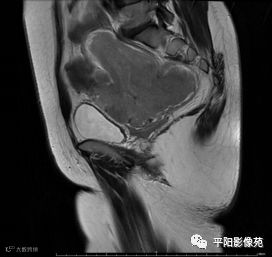

MRI表现

T2矢状位

(宫腔内见金属节育环伪影)宫颈区见不规则形等T1稍长T2信号软组织肿块,DWI序列呈明显高信号,大小约为3.87cmX2.64cm,双侧宫颈基质低信号环连续性中断,病灶向子宫右后上方生长,周围脂肪间隙模糊,增强扫描明显强化,强化程度低于子宫及宫颈实质;子宫后方、子宫直肠间隙见不规则形长T1长T2信号软组织肿块,DWI序列呈高信号,大小约10.12cmX4.82cmX10.29cm,病灶呈分叶状,向下方生长与宫颈分界不清,与直肠分界尚清,增强扫描明显不均匀强化。